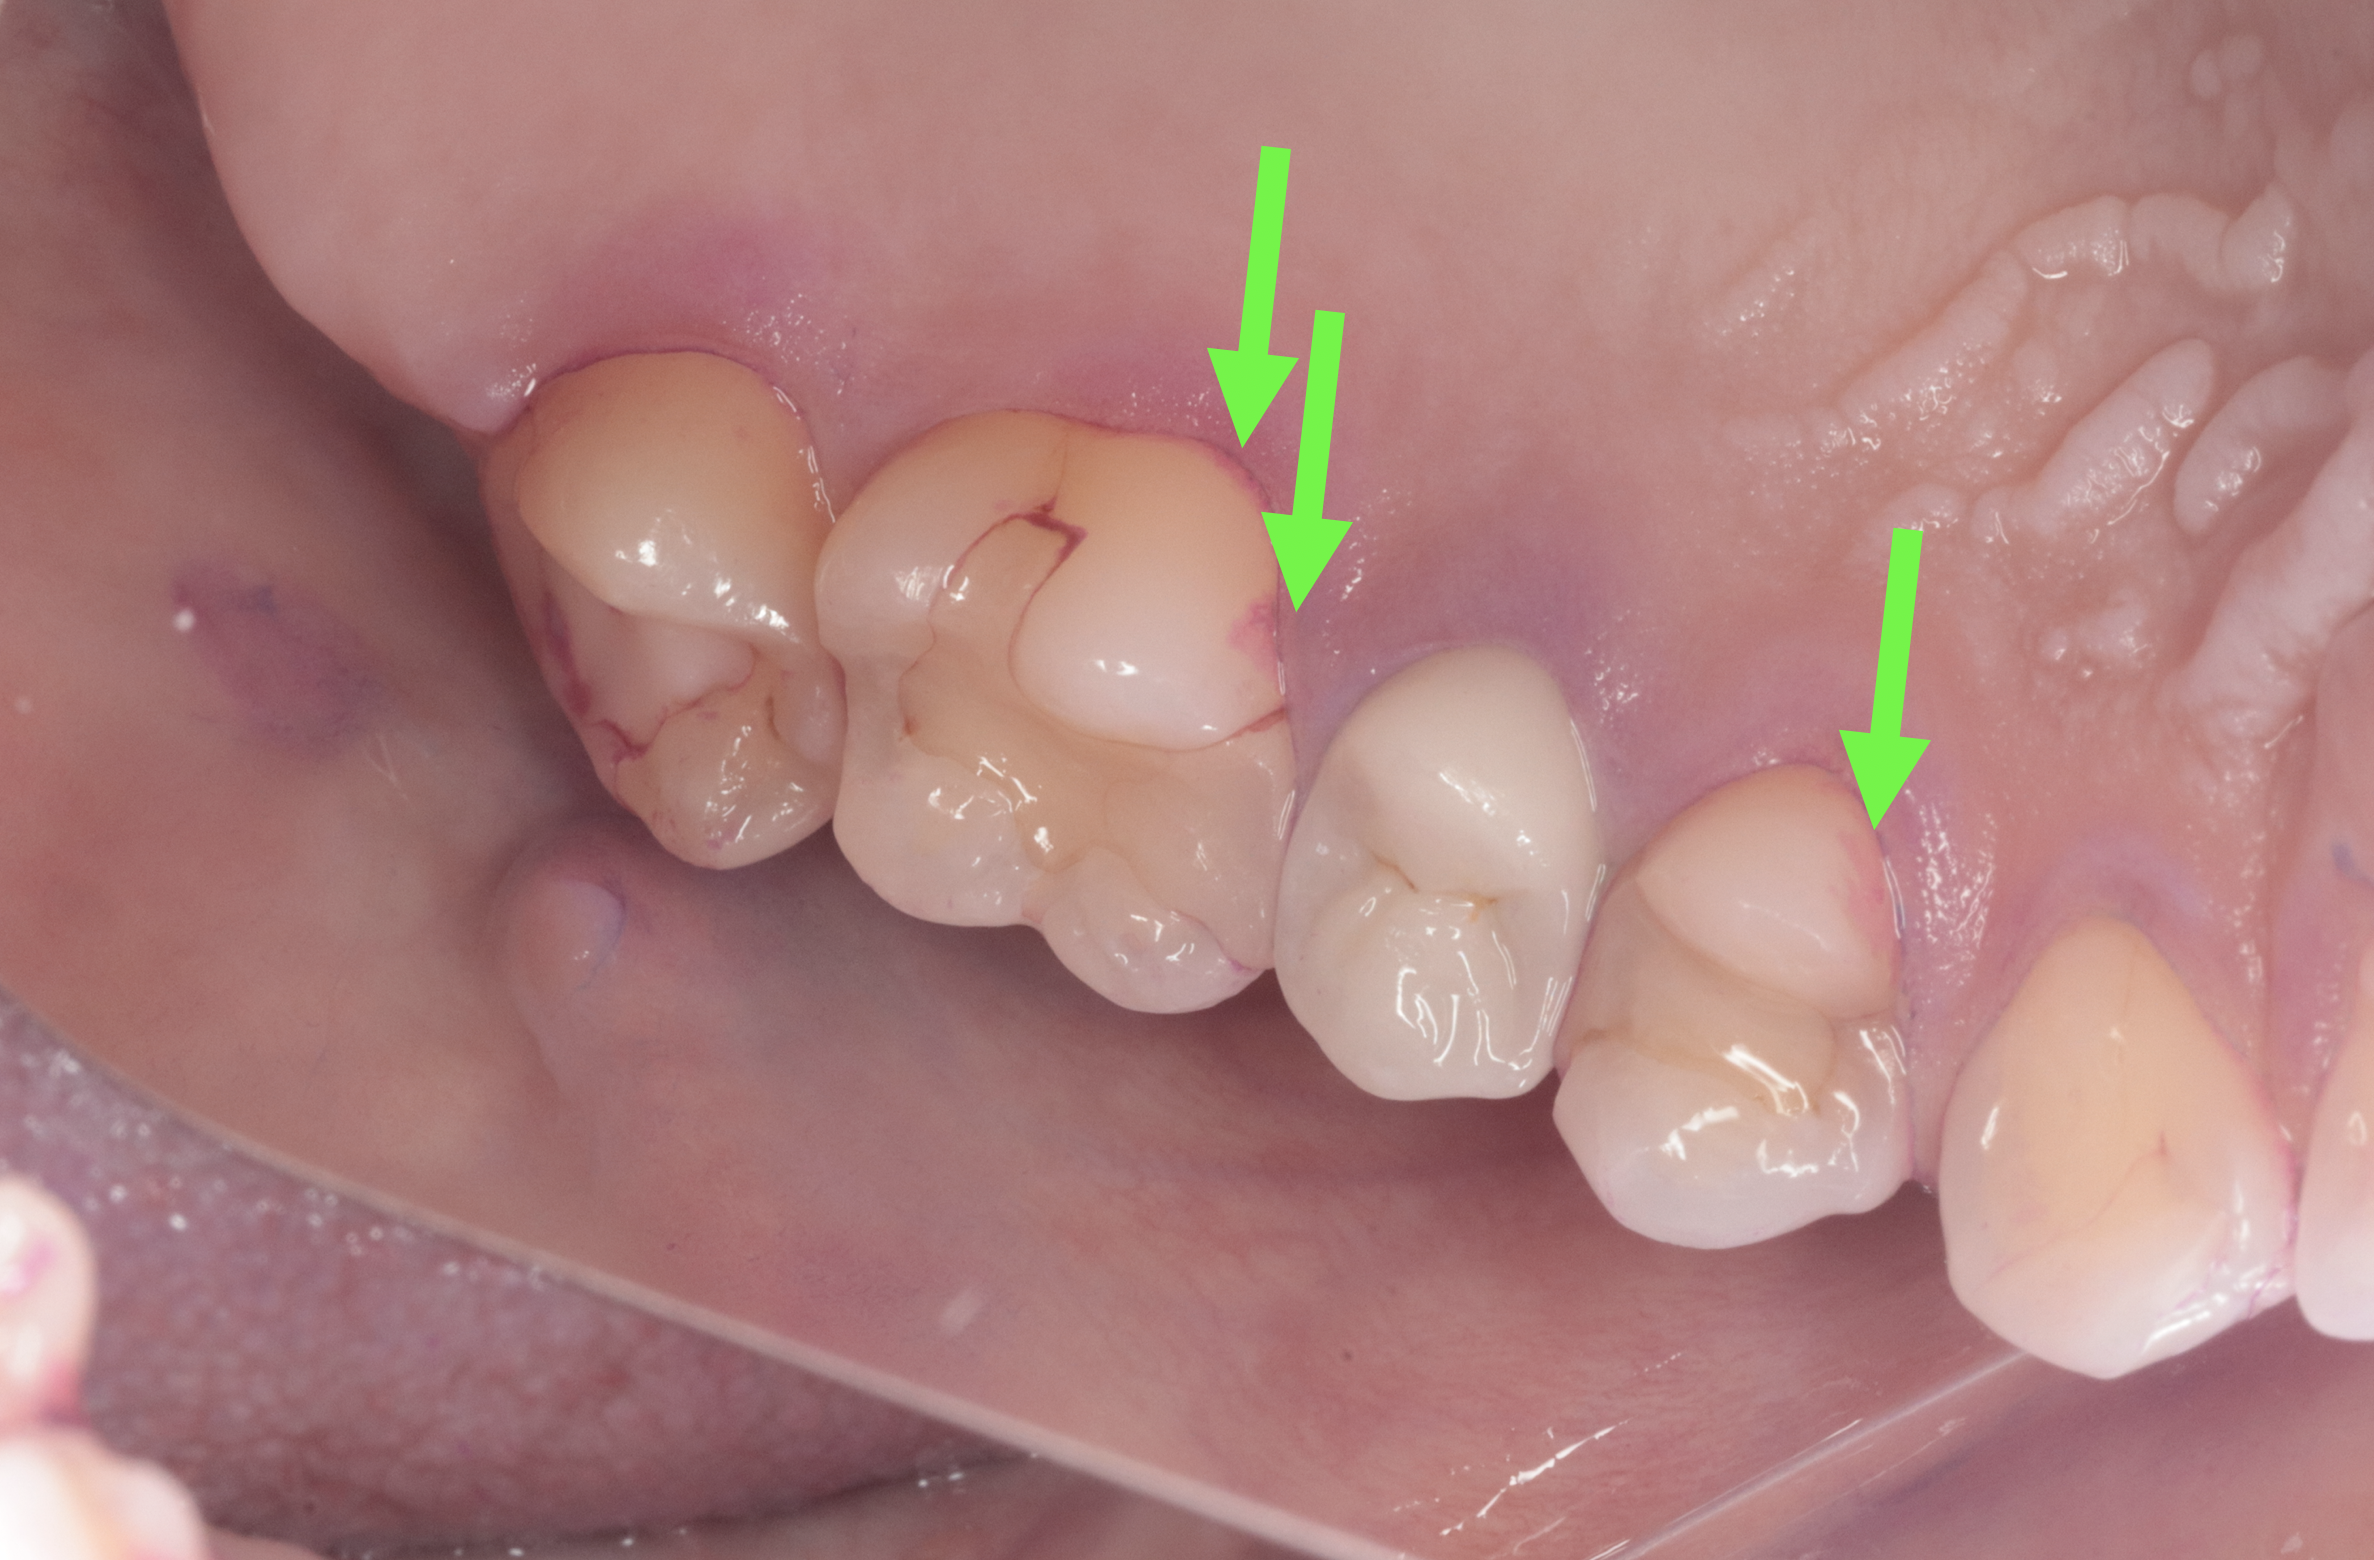

画像真ん中の少し白いかぶせものがジルコニアです、セットして数年が経過しています。

いつも綺麗に歯ブラシしてきてくださいますが、矢印のところにプラークが残っています。

両方の写真の、かぶせものをご覧ください。

そう、、、プラークの付着が見られないのがお分かりいただけますでしょうか。